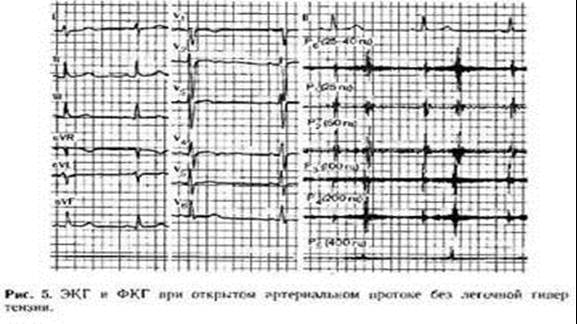

Об‘активно. Стан дитини середньої важкості. t 36,3 Шкіряні покриви бліді, „мармуровий” малюнок шкіри, періоральний та періорбітальний ціаноз. Задишка до 50 за хв.. Аускультативно – жорстке дихання, вологі та сухі хрипи. Пульс 146 за хв., ритмічний. Серцевий поштовх розлитий. Межі серця розширені вліво. Аускультативно – I тон на верхівці звучний,II акцентований та роздвоєний над легеневою артерією, систолодіастолічний шум в лівій підключичній ділянці. Печінка + 2 см. На ЕКГ – гіпертрофія лівого передсердя та шлуночка. На рентгенограмі – кардіомегалія за рахунок гіпертрофії лівого передсердя та шлуночка, підсилення легеневого малюнку, корені легень застійні.

На ЕхоКГ – поток крові з місця біфуркації легеневої артерії в протилежному (до датчика).

Рентгенографічно – збільшення серця за рахунок лівого шлуночку, вип’ячування дуги легеневої артерії. Легеневий малюнок підсилений.